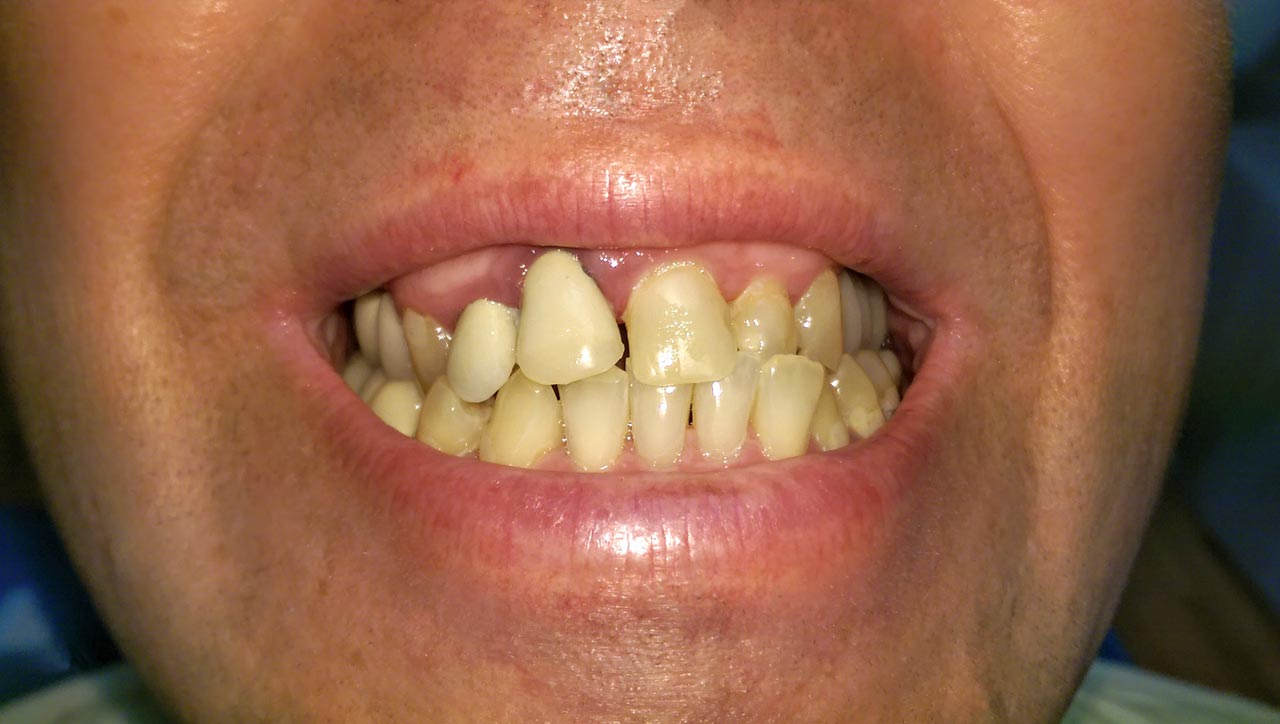

Rágófunkció esztétikus helyreállítása azonnalterhelhető svájci IHDE implantátumokkal és porcelán koronákkal.

A régóta fennálló foghiány és a mozgó fogak miatt a páciens nem tudott jól rágni és harapni, illetve mosolyogni sem mert már jó ideje. A leggyorsabb és a legesztétikusabb megoldás az ilyen esetekre az IHDE azonnal terhelhető implantátumok behelyezése, és az azokra rögtön elkészített porcelán koronák elkészítése.

A teljes munka - az implantáció, a végleges koronák elkészítése - 5 munkanapot vett igénybe.